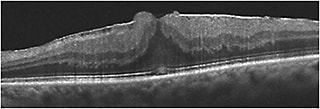

On OCT, a LMH has the following characteristics1,2:

• An irregular inner foveal contour;

• A defect in the inner retina layers of the fovea;

• Intraretinal splitting (schisis) between inner and outer retina;

• Intact photoreceptors; and

• Usually epiretinal membrane or thickened residual posterior hyaloid (Figure 1).

Figure 1. Lamellar macular hole associated with ERM. Note the loss of inner retinal tissue, schisis, and intact photoreceptors.